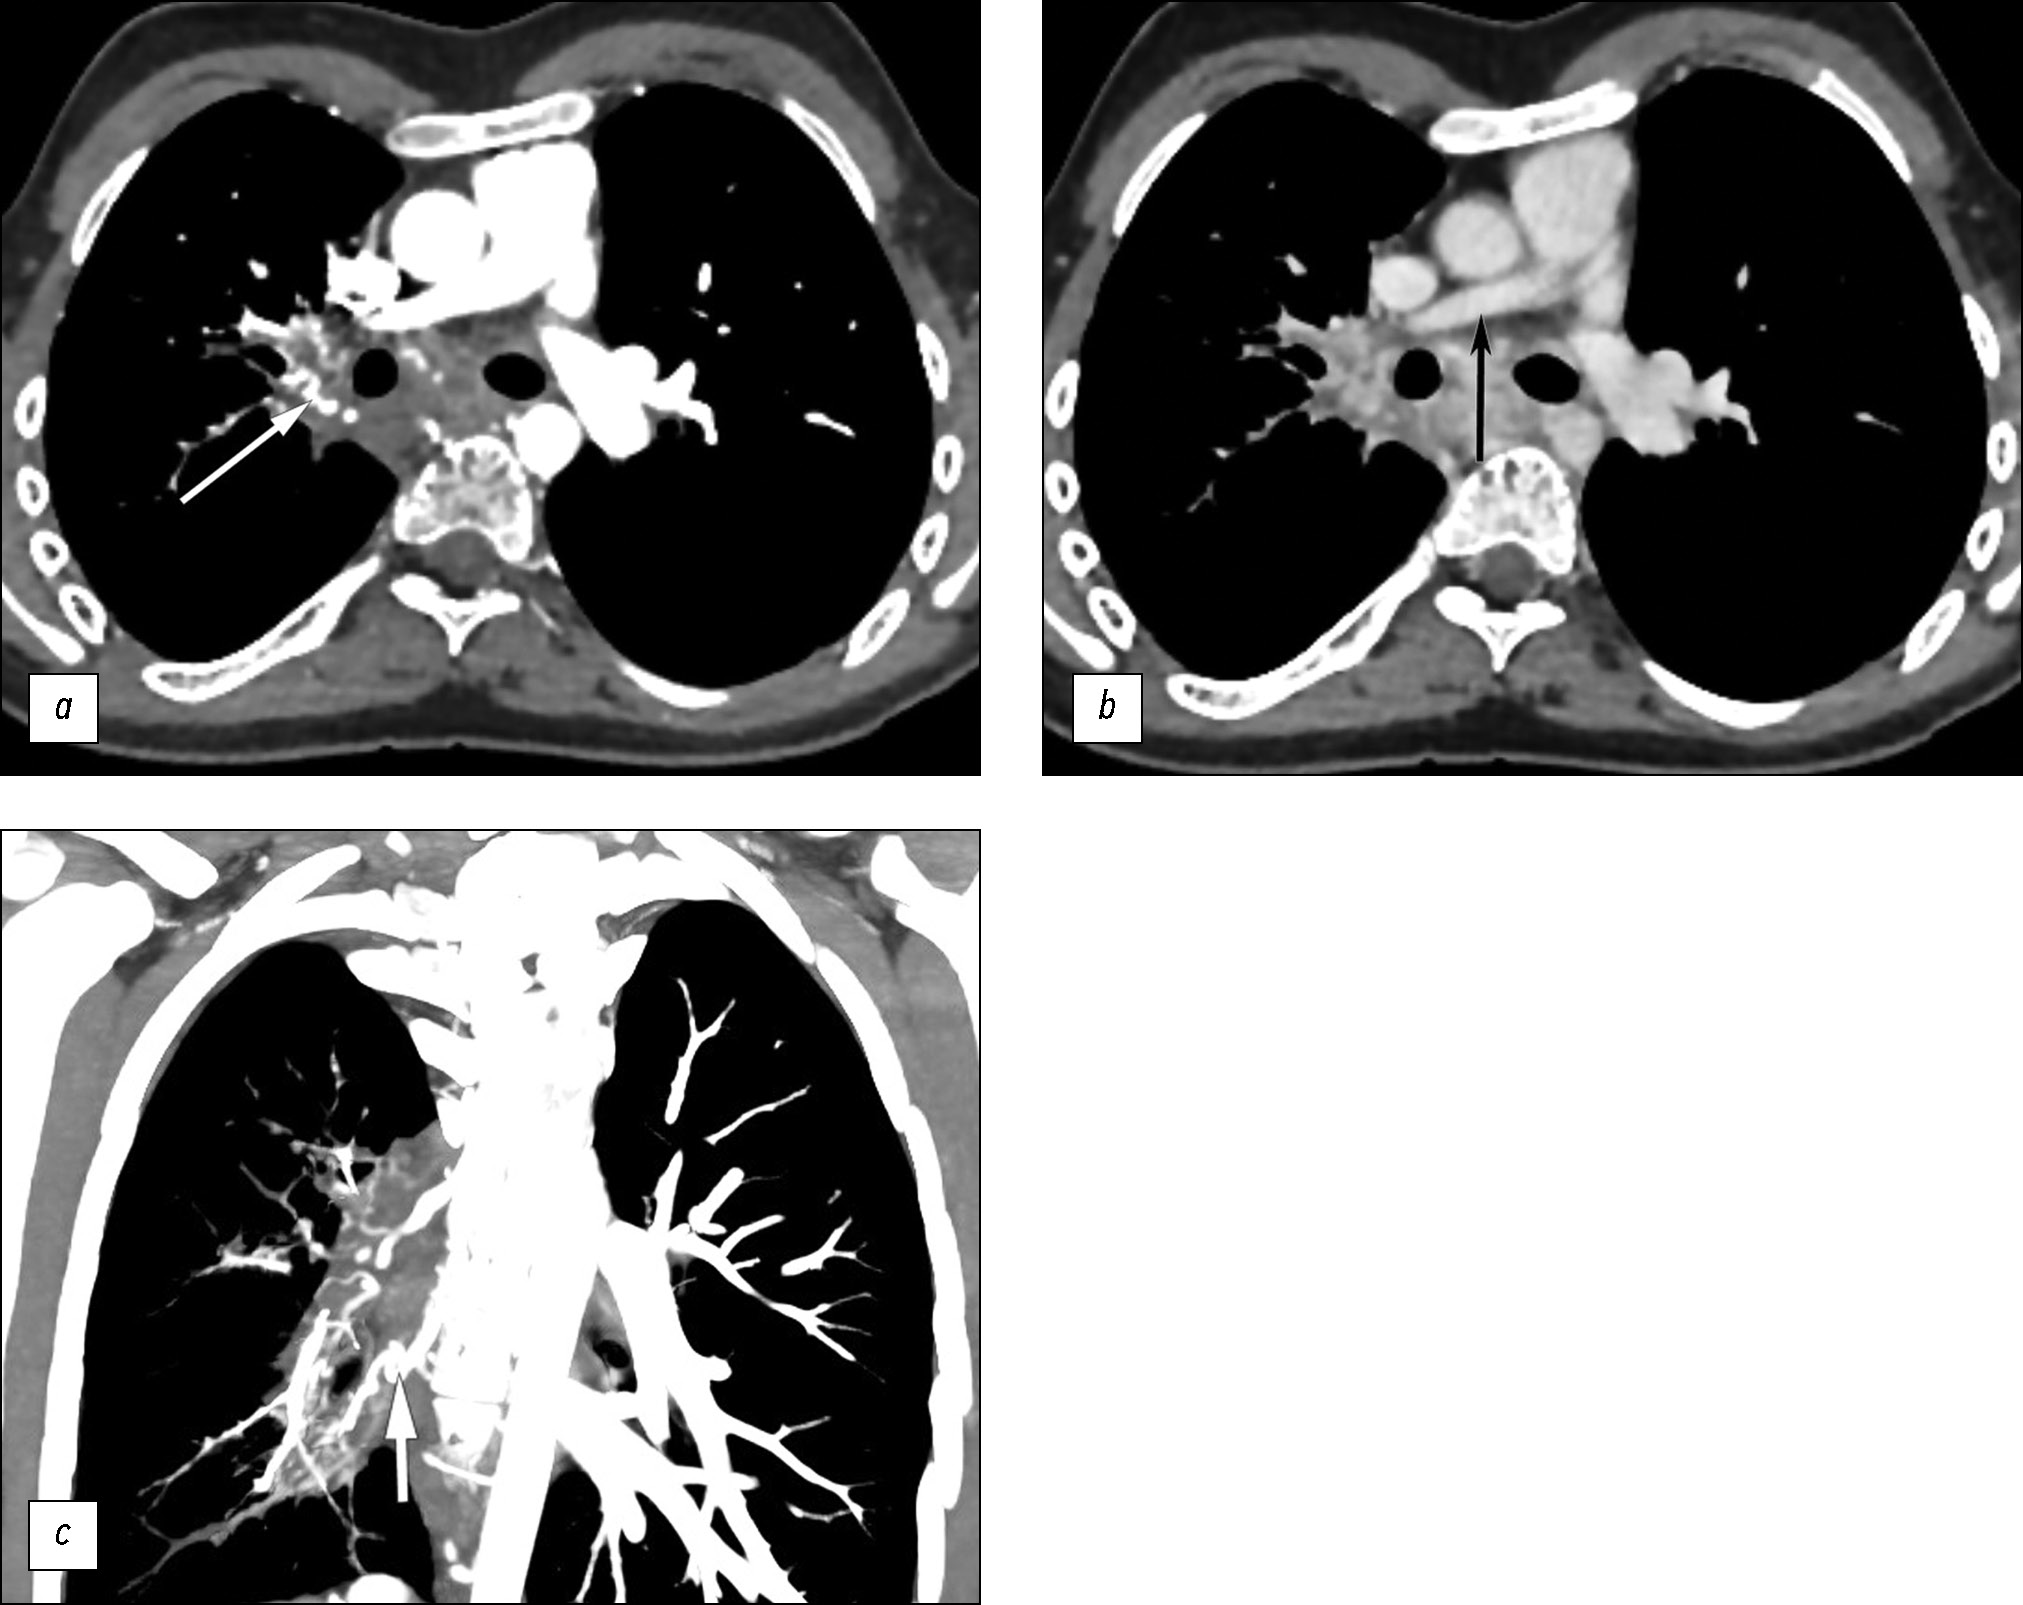

Arterial and venous phase scanning along the margins of the right main bronchus revealed multiple dilated, tortuous arterial and venous vessels (bronchial and intercostal) in the intrathoracic lymph nodes; without contrast enhancement, they were previously interpreted as manifestations of intrathoracic lymphadenopathy (Fig. 3). The decreased diameter of the right pulmonary artery to 7 mm (vs. 14 mm on the contralateral side) and absence of contrast enhancement in the right pulmonary veins were clearly visualized in the three-dimensional reconstruction of the heart (Fig. 4).

Fig. 3. Computed tomography of the lungs; (a, b) axial plane; c: coronal plane. White arrows: multiple vascular collaterals along the bronchial contour. Black arrow: hypoplasia of the right pulmonary artery.

Fig. 4. Absence of the right pulmonary veins (white arrows); (a) computed tomography of the lung in the coronal plane; (b) computed tomography of the lung in the axial plane; (c) three-dimensional reconstruction of the heart.